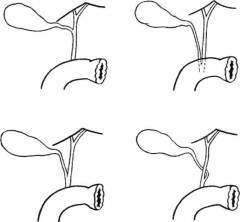

Желчные протоки и проток поджелудочной железы у разных людей могут иметь различную длину, соединяются между собой и впадают в двенадцатиперстную кишку по-разному. Иногда, помимо основного протока, от тела желчного пузыря отходят дополнительные. Врачу приходится учитывать эти особенности во время проведения лапароскопии.

Варианты соединения желчевыводящих протоков.